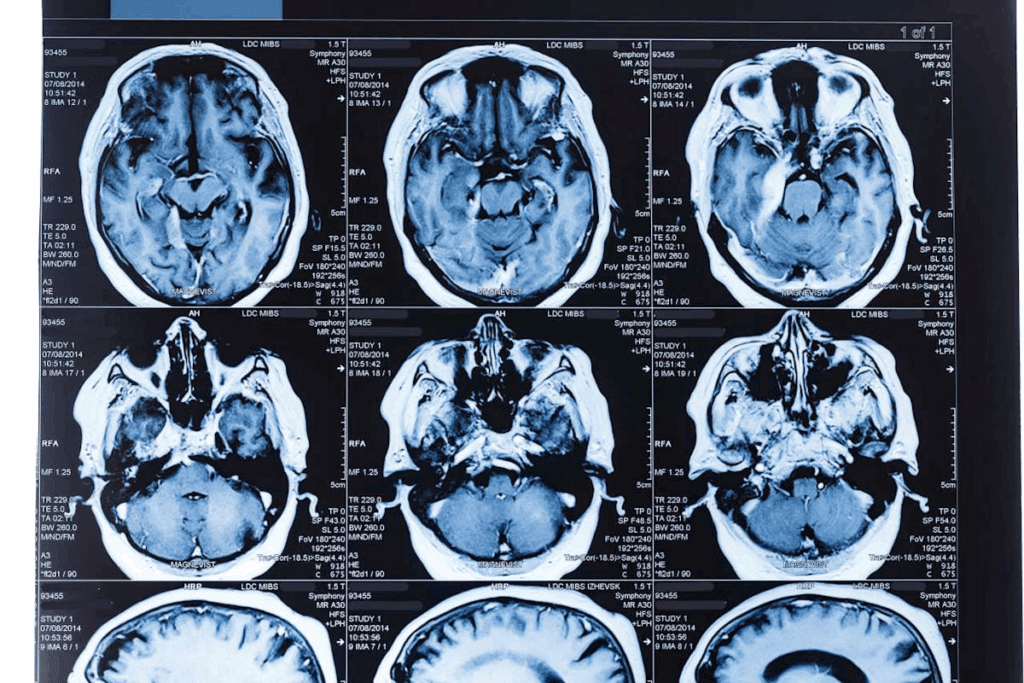

MRI Scans: The Gold Standard for Brain Tumor Diagnosis

MRI scans are the top choice for finding brain tumors in kids. They can spot tumors and normal brain tissue with great accuracy. This tool has changed how we look at brain tumors in kids, helping doctors plan better treatments.

How MRI Differs from CT Scans

MRI and CT scans are both used to see inside the body. But they work in different ways. MRI uses magnets and radio waves to show detailed brain pictures. CT scans use X-rays.

This makes MRI better at showing soft tissues like tumors. It’s a big plus for finding and understanding brain tumors.

Here are some main differences between MRI and CT scans:

- MRI doesn’t use harmful radiation, making it safer for kids.

- It shows soft tissues like tumors and nerves better than CT scans.

- MRI can also show how blood flows and tissues work, not just what they look like.